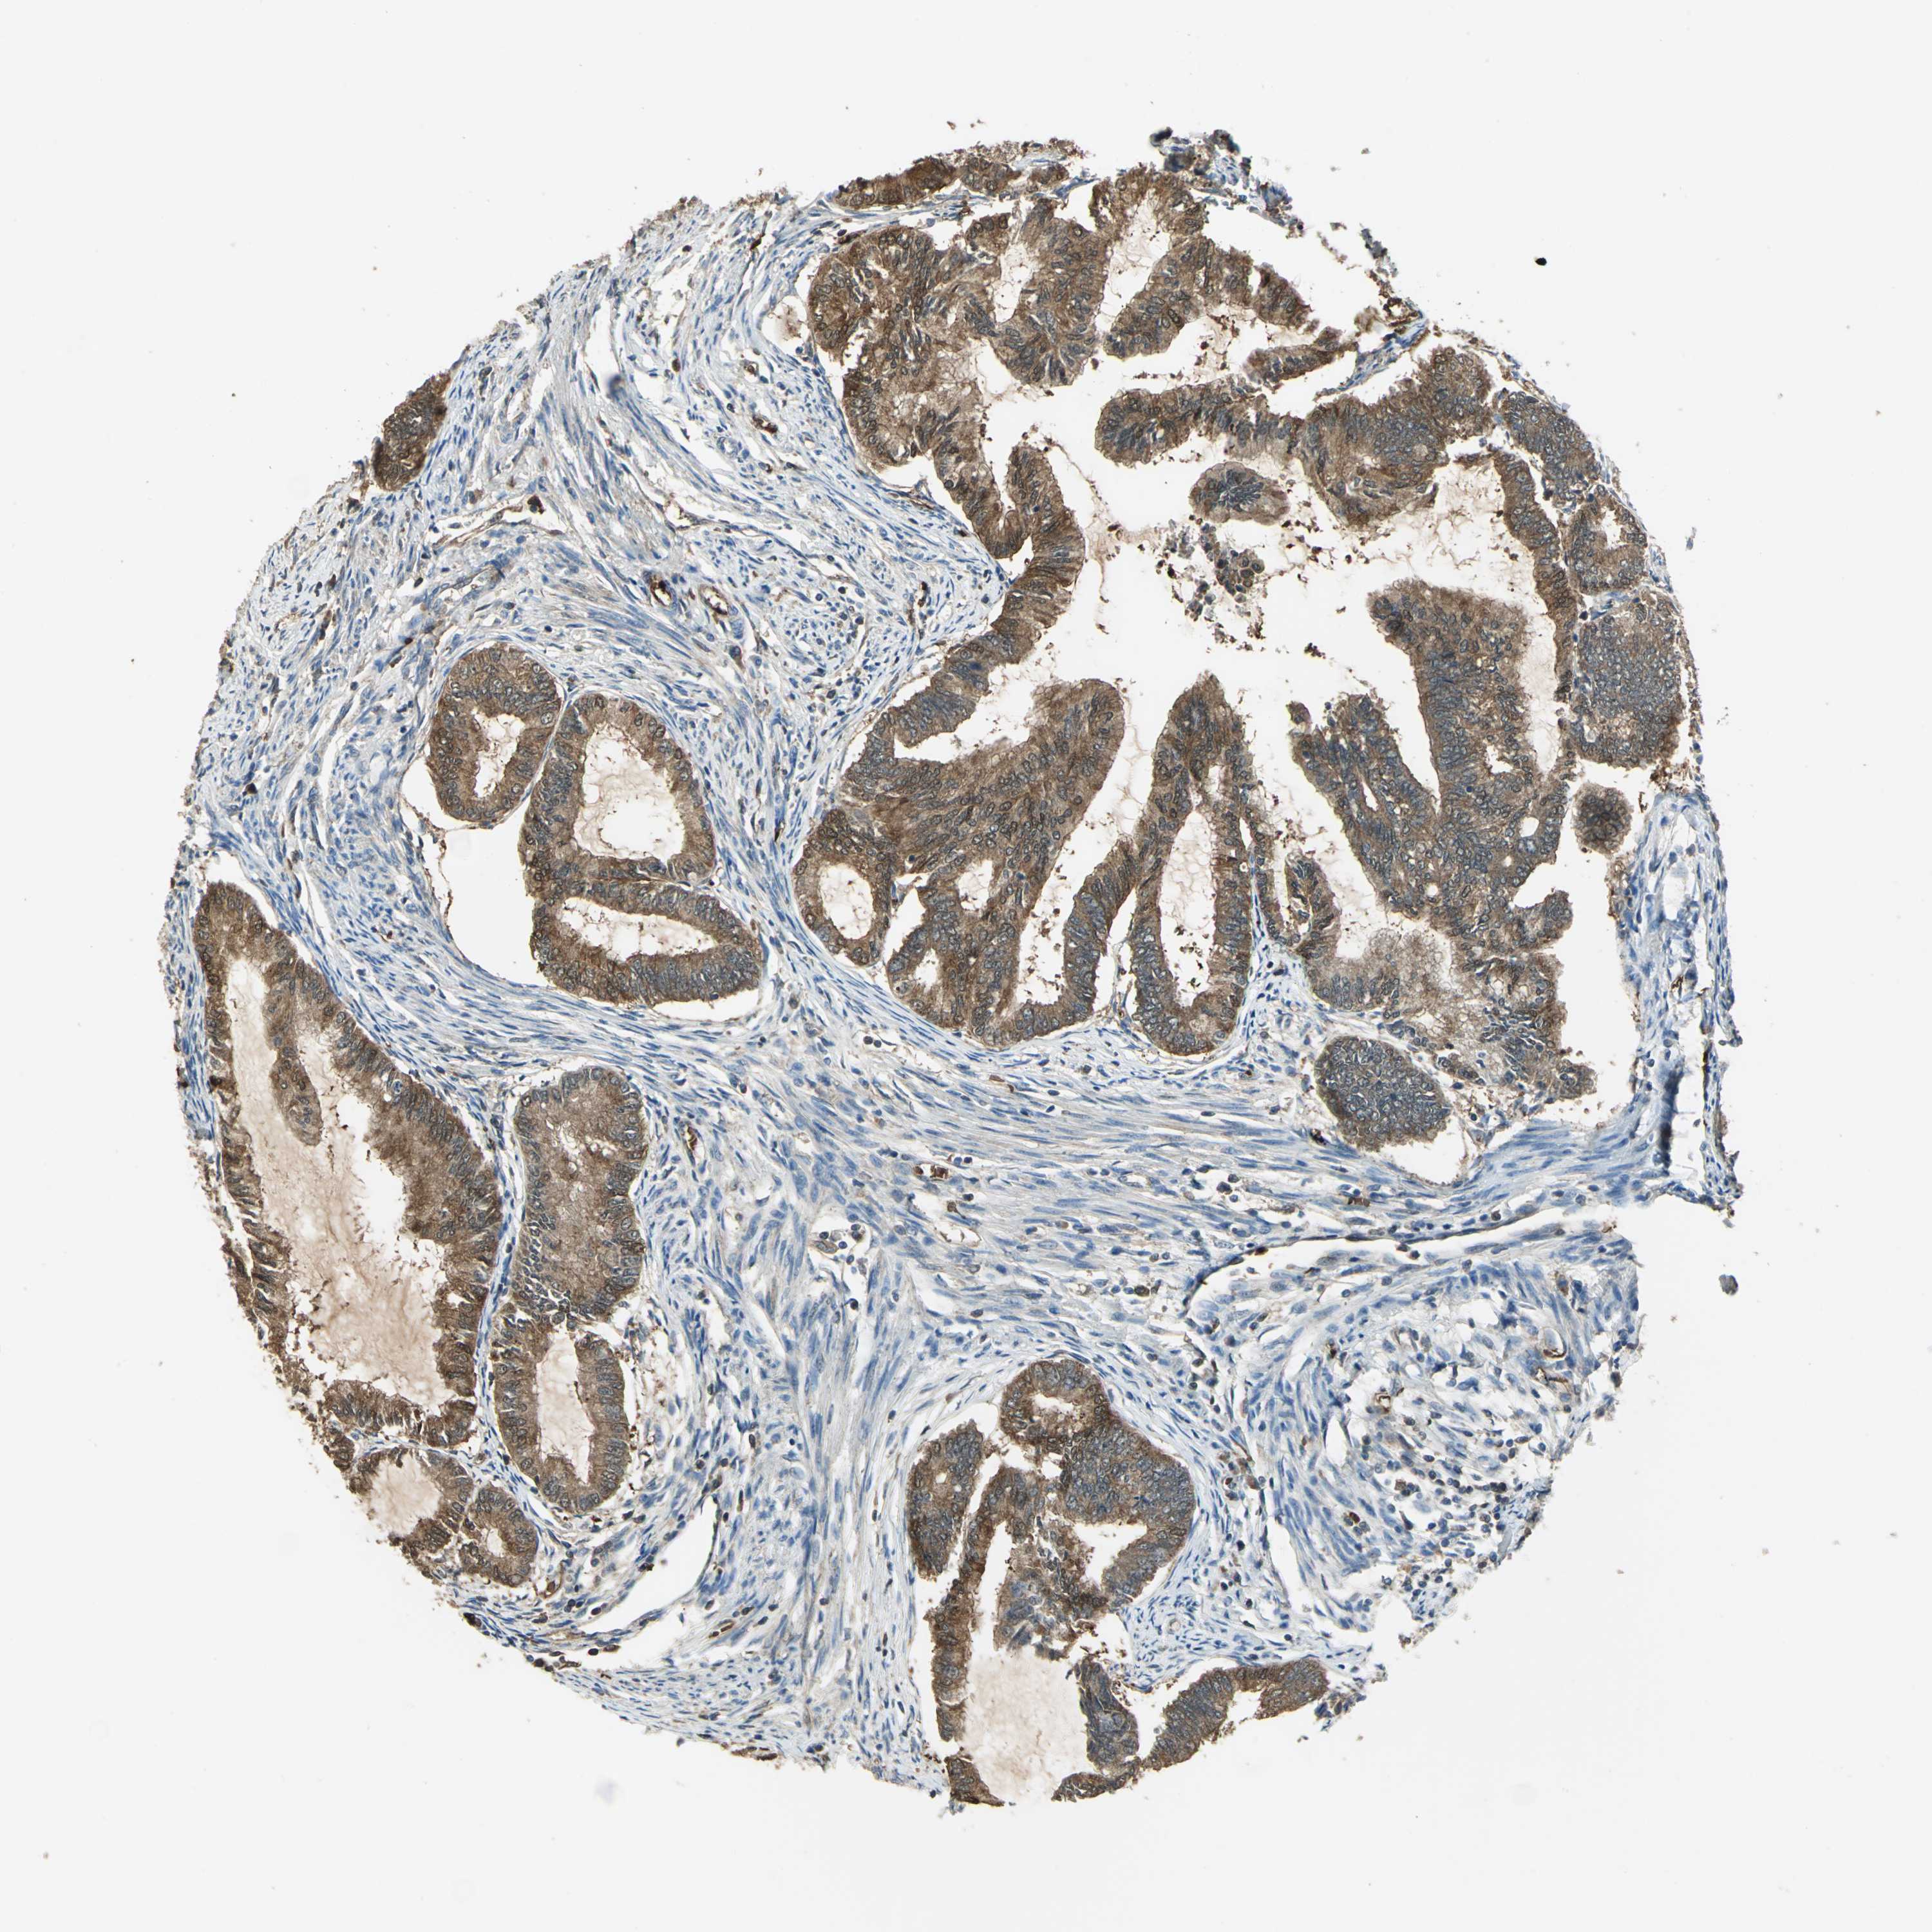

ENDOMETRIAL CANCER - Protein expressioni

A mouse-over function shows sample information and annotation data. Click on an image to view it in a full screen mode. Samples can be filtered based on level of antibody staining by selecting one or several of the following categories: high, medium, low and not detected. The assay and annotation is described here.

Note that samples used for immunohistochemistry by the Human Protein Atlas do not correspond to samples in the TCGA dataset.

Antibody stainingi

Antibody staining in the annotated cell types in the current human tissue is reported as not detected, low, medium, or high, based on conventional immunohistochemistry profiling in selected tissues. This score is based on the combination of the staining intensity and fraction of stained cells.

Each image is clickable and will lead to virtual microscopy that enables deeper exploration of all samples and also displays staining intensity scores, fraction scores and subcellular localization as well as patient and tissue information for each sample.

Antibody HPA006308

Antibody HPA071064

Staining

High

Medium

Low

Not detected

Intensity

Strong

Moderate

Weak

Negative

Quantity

>75%

75%-25%

<25%

None

Location

Nuclear

Cytoplasmic/membranous

Cytoplasmic/membranous,nuclear